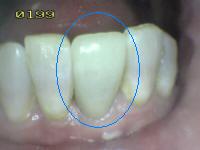

2 |

Sellador completo |